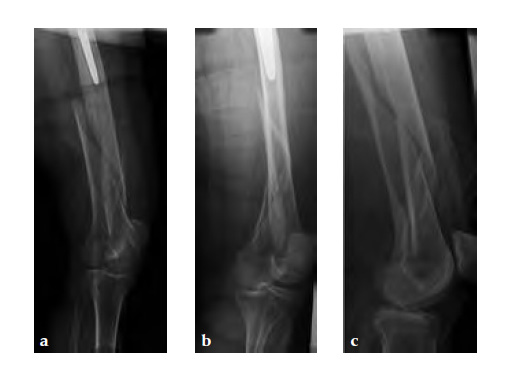

Case 1: A 78-year-old female sustained a periprosthetic fracture, Vancouver type C, 9 years after a total hip arthroplasty.